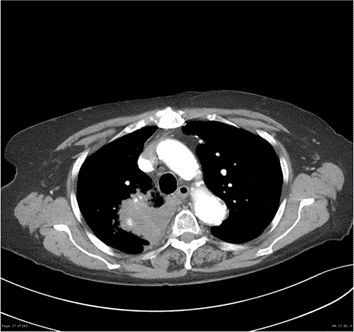

Small cell lung cancer.

Very nice presentation and learning procedure. Happy to learn something about Small cell carcinoma of the lung.